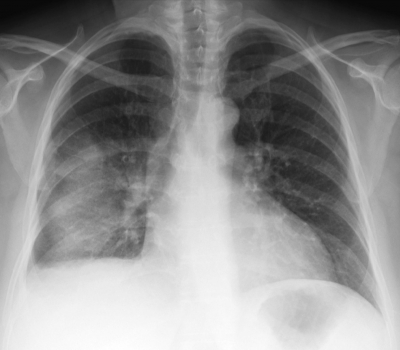

身長 151 cm、体重 70 kg。体温 36.8 ℃。脈拍 92/分、整。血圧 130/102 mmHg。呼吸数 18/分。SpO2 94 %(room air)。呼吸困難の原因は胸水貯留であると考え、入院の上、胸腔穿刺を行い胸水を排液した。呼吸困難は一時的に改善したが、 穿刺1時間後に強い呼吸困難と泡沫状の喀痰がみられ、SpO2 92 %(鼻カニューラ2L/分 酸素投与下)となった。 穿刺2時間後、症状はさらに悪化し、SpO2 85 %(マスク8L/分 酸素投与下)となったため気管挿管を行った。来院時と胸腔穿刺1時間後の胸部エックス線写真と胸部CTとを示す。

胸腔穿刺1時間後